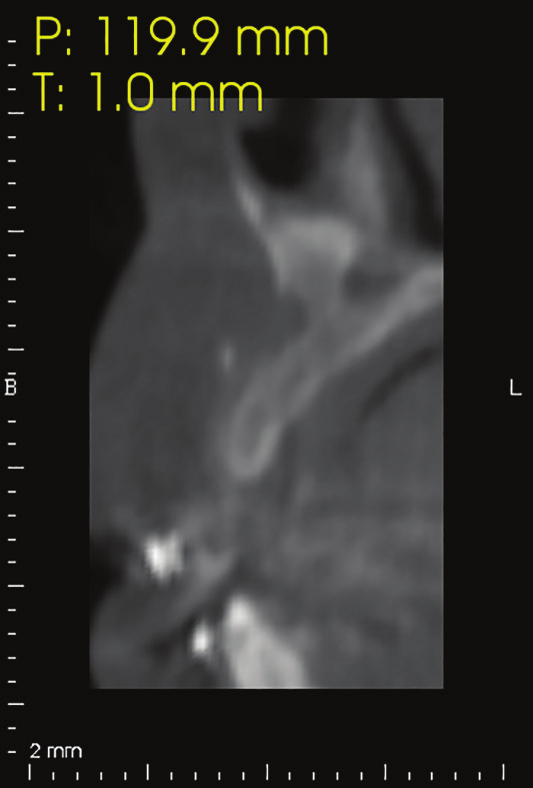

Figure 29: 5 months postoperative CBCT cross-sectional view revealed bone growth insuring an adequate placement of implant in an ideal position.

A 38 years-old female patient came to our clinic with swelling upper anterior area, she was medically fit with no health problems. The patient underwent an orthodontic treatment for 2 years and was about to remove it and place retainer. Intraoral examination showed swelling apical area of tooth no 7. The periapical x-ray and CAT view revealed a lateral perforation on the same mentioned tooth with a well circumscribed radiolucency in apical area (Fig.20, 21). Pain on percussion and slight mobility were noted. A surgical enucleation and extraction of tooth no 7 were conducted (Fig.22, 23, 24). 3 months postoperative CAT view shows an advanced horizontal bone loss with no recurrence of lesion in the area (Fig. 26), clinically after reflection of mucoperiosteal flap, the situation confirmed the CAT image (Fig.25) , the case was planned for PRF -associated bovine bone technique replacing the aggressive autologous bone graft procedure. After collection of PRF from patient blood culture, a first layer of L-PRF covering the bovine bone associated PRF complex (sticky bone) was done (Fig.27). The second layer of L-PRF came to cover the cross-linked collagen membrane (Fig. 28).

5 months postoperative CBCT cross-sectional view revealed bone growth insuring an adequate placement of implant in an ideal position.